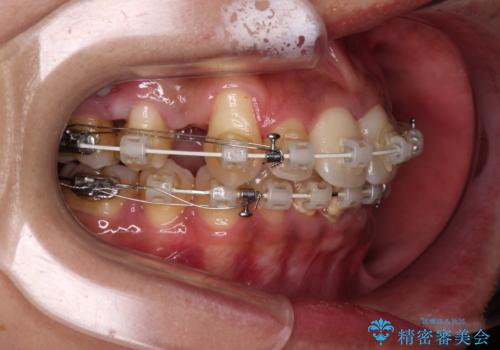

- 審美装置

- 2年6ヶ月

- 10-30回

上下前歯部叢生のスペース獲得のため、上下顎左右小臼歯各1歯(計4本)を抜歯して、ワイヤー装置にて矯正治療を行うこととしました。

上下の正中位置が大きくずれていたため、上下正中が合わないまま終了することが予想されましたが、思っていた以上にスムーズに歯が移動し、満足いただける仕上がりとなりました。